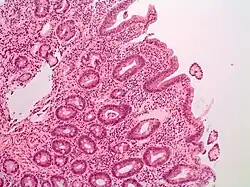

Pathology

The Marsh-Oberhuber classification is commonly used to assess the pathological changes seen in coeliac disease.[9] Marsh originally described three different stages of coeliac disease lesions in 1992. These three stages were updated in 1999 by Oberhuber to further classify stage three.[60][61] The Marsh classification is based on three histological features: intraepithelial lymphocytes count above 25/100 enterocytes (intraepithelial lymphocytosis), elongated crypts of Lieberkuhn (crypt hyperplasia), and shortening or absence of villi (villous atrophy). As these features can be seen in other disorders, they are not diagnostic for coeliac disease without serological or clinical indications.[60] Current guidelines do not recommend a repeat biopsy unless there is no improvement in the symptoms on a gluten free diet.[52]

| Type | Increased intraepithelial lymphocytes | Crypt hyperplasia | Villi |

|---|---|---|---|

| 0 (normal) | <40 lymphocytes/100 enterocytes | Normal | Normal |

| 1 (infiltrative) | >40 lymphocytes/100 enterocytes | ||

| 2 (hyperplastic) | Increased | ||

| 3a (destructive) | Mild atrophy | ||

| 3b (destructive) | Moderate atrophy | ||

| 3c (destructive) | Complete atrophy |